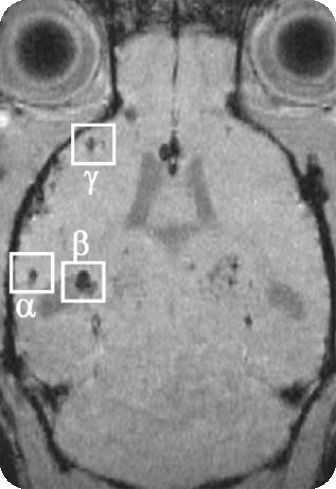

4、SWI磁敏感成像

磁敏感成像可大大提高磁敏感性,可用于檢測(cè)老年癡呆小鼠模型粥狀淀粉沉積斑塊,評(píng)價(jià)藥物作用療效。

老年癡呆小鼠腦部的磁敏感成像: